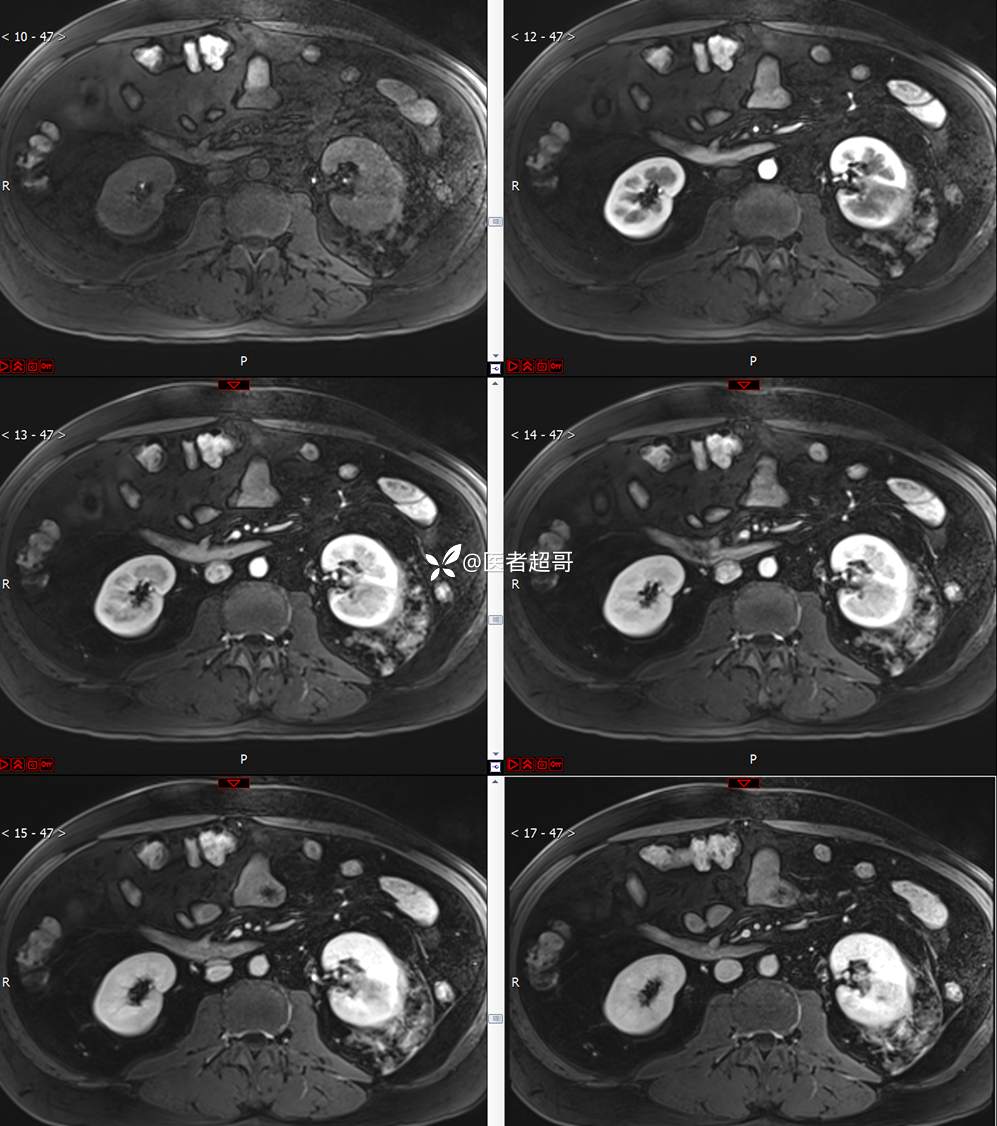

主 诉:查体发现左肾肿物9天。

现病史:患者9天前于附属医院行常规腹部CT检查时,发现左肾占位性病变并肾周脂间隙软组织增多,自述无明显腰腹部不适,无尿频、尿急、尿痛及肉眼血尿,未予特殊治疗,患者近期无头晕头迷,胸闷气急,腹胀腹泻及其他部位明显不适,遂至我院就诊,门诊以“肾肿物”收入院,患者自发病以来,精神可,睡眠饮食可,大便正常,体重无明显减轻。